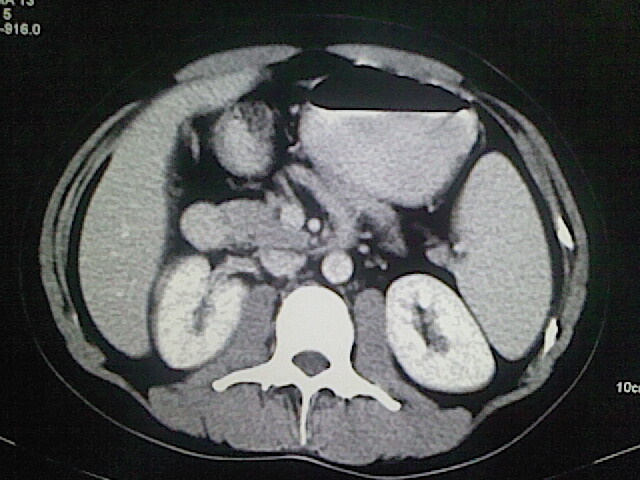

以下是引用卜一在2009-3-14 9:49:00的发言:[br]胆囊萎缩,胆囊壁不规则增厚,内部结构模糊,增强明显强化。另:肝左叶外侧段肝囊肿。支持:慢性胆囊炎!高度可疑:胆囊癌!

以下是引用余辉在2009-3-14 8:48:00的发言:[br]1)慢性胆囊炎。2)肝左叶外侧段肝囊肿。3)脂肪肝。[br]支持,胆囊萎缩,密度增高,不知b超具体有何提示,钙胆汁?结石?

以下是引用jiangjing在2009-3-14 10:18:00的发言:[br]1)慢性胆囊炎。2)肝左叶外侧段肝囊肿。3)脂肪肝。4.】建议行肝功能检查